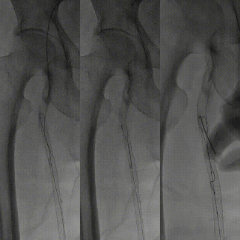

手术过程

图:推送saber球囊

图:开通腘动脉主干

图:4mm/5mm球囊顺序行股腘动脉PTA,3mm球囊行腓动脉PTA

图:由肱动脉先行股动脉支架置入,而后顺行穿刺股总动脉

图:胫腓干夹层,置入3.5mm*35mm药涂支架(冠脉支架)